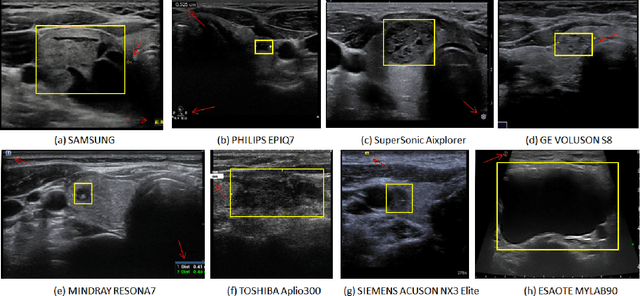

Abstract:Ultrasound (US) is the primary imaging technique for the diagnosis of thyroid cancer. However, accurate identification of nodule malignancy is a challenging task that can elude less-experienced clinicians. Recently, many computer-aided diagnosis (CAD) systems have been proposed to assist this process. However, most of them do not provide the reasoning of their classification process, which may jeopardize their credibility in practical use. To overcome this, we propose a novel deep learning framework called multi-attribute attention network (MAA-Net) that is designed to mimic the clinical diagnosis process. The proposed model learns to predict nodular attributes and infer their malignancy based on these clinically-relevant features. A multi-attention scheme is adopted to generate customized attention to improve each task and malignancy diagnosis. Furthermore, MAA-Net utilizes nodule delineations as nodules spatial prior guidance for the training rather than cropping the nodules with additional models or human interventions to prevent losing the context information. Validation experiments were performed on a large and challenging dataset containing 4554 patients. Results show that the proposed method outperformed other state-of-the-art methods and provides interpretable predictions that may better suit clinical needs.